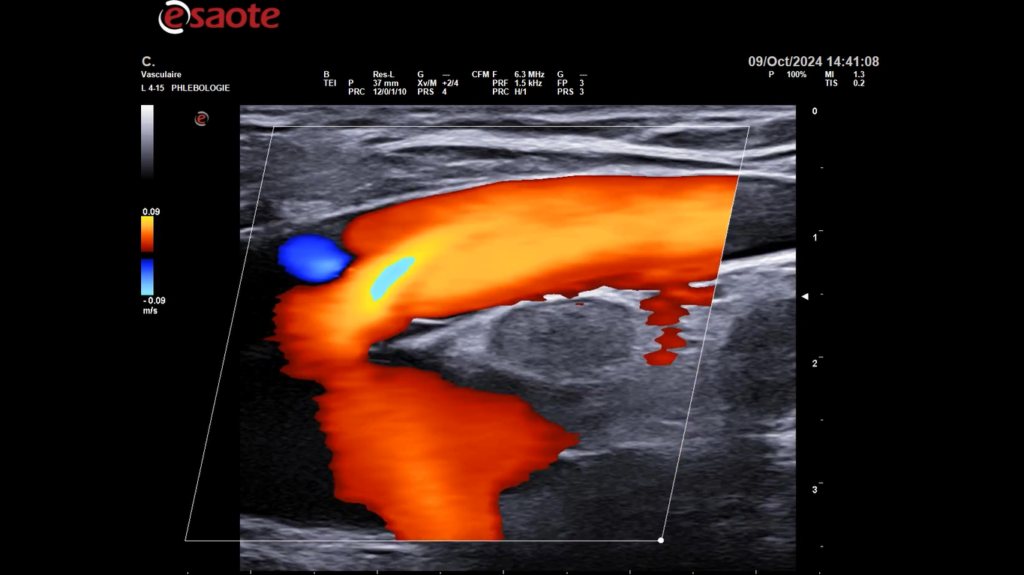

Formation pratique à la sclérothérapie échoguidée à la mousse – Expert 3D – 28 novembre 2025

L’EIS vous propose une formation d’une journée, le vendredi 28 novembre 2025, directeur du cours : Dr Mario Sica, cette session vous permettra d’optimiser la prise en charge diagnostique et thérapeutique de vos patients grâce à une approche avancée de la sclérothérapie échoguidée en 3D.